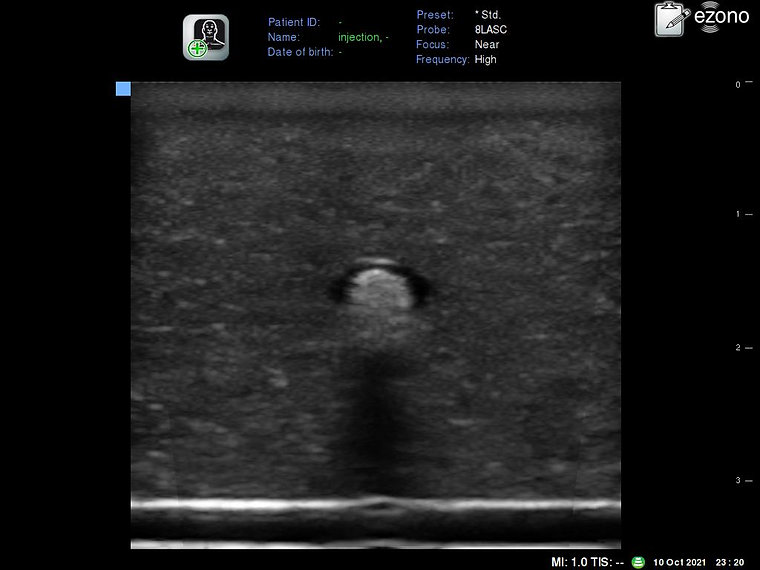

INTERNAL LANDMARKS : Nerve

INJECTION CHARACTERISTICS

Tissue: <5 PSI for fluid flow to occur. Intraneural: >20 PSI for fluid flow to occur